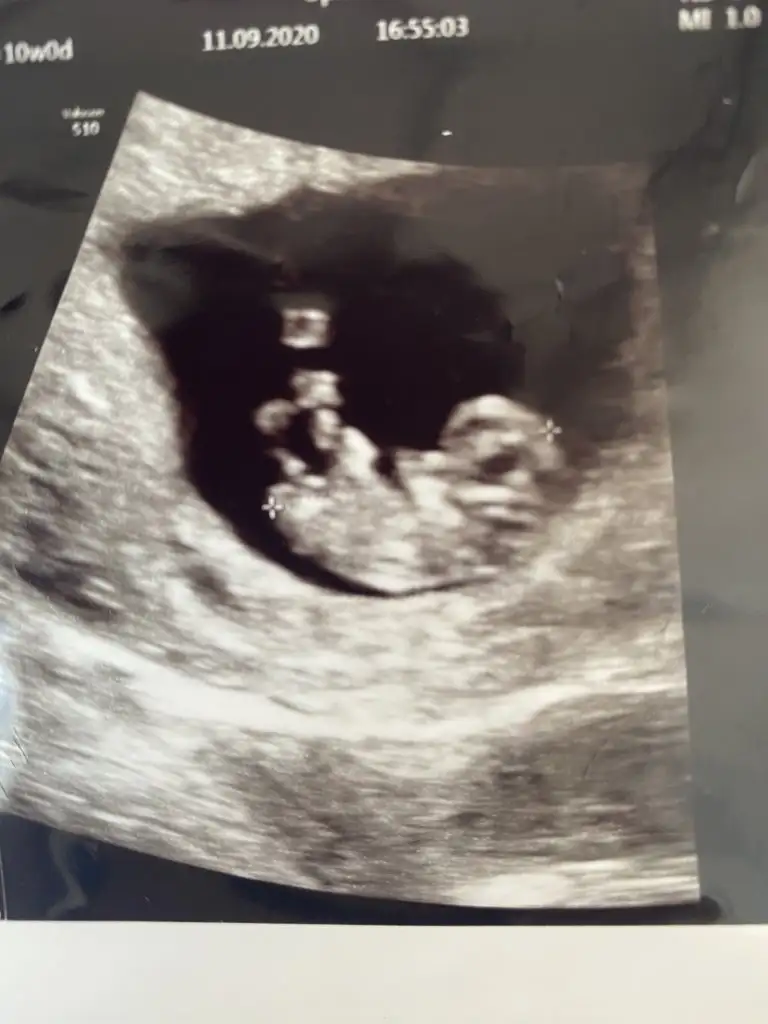

Kimse cevap yazmıyor nedenseBana da tahminde bulunabilir misiniz 10 haftalık görüntü Eki Görüntüle 2698547